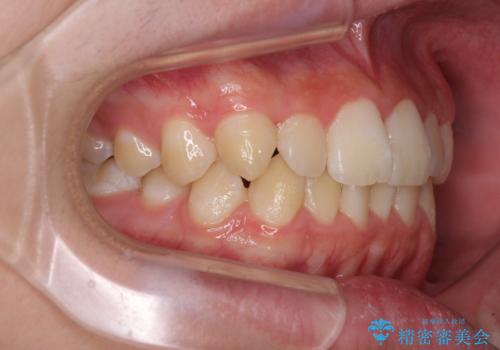

- 上下前歯のデコボコを気にして来院された患者様です。

高校2年生の後半であったため、受験も近く、大学に入学してからでも良いのではと提案しました。

本人の「しっかりと装着する」という強い意志があったため、来院の負担を少なく受験までに終えられるよう、インビザラインにて矯正治療を行うこととしました。